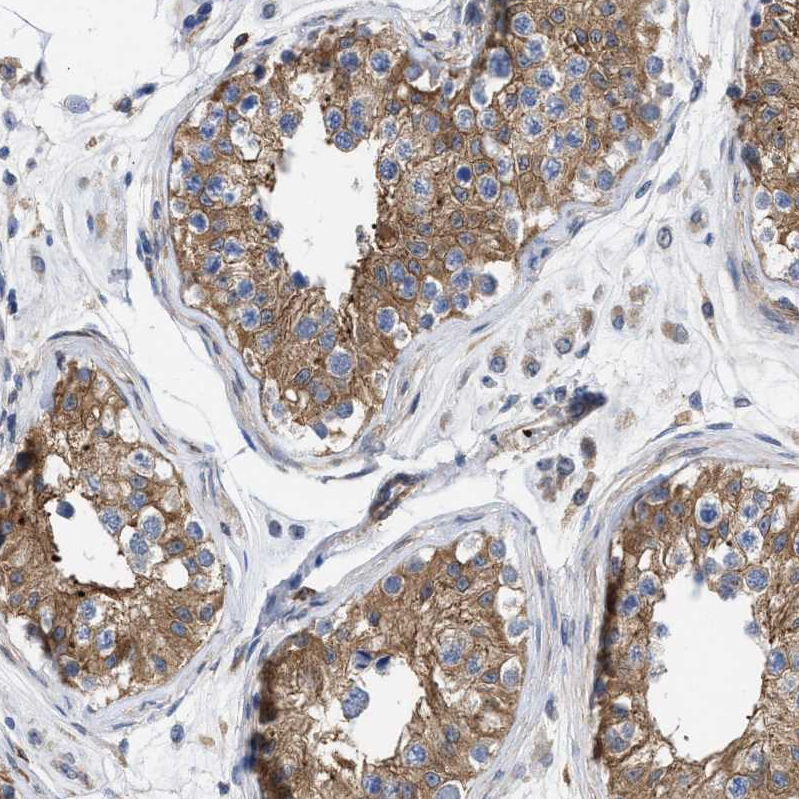

Immunohistochemical staining of human cerebellum shows strong cytoplasmic positivity in Purkinje cells.